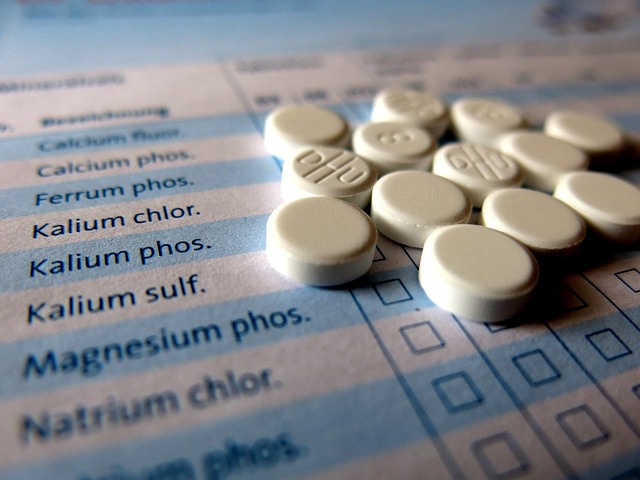

When seeking Find Functional Medicine in Bloomington-Bedford, patients are often looking for a holistic approach to their health and wellness. Bloomington-based functional medicine clinics offer a range of services designed to address the root causes of illness, rather than just treating symptoms. These practices prioritize natural solutions for your health, utilizing preventive medicine techniques tailored to each individual’s unique needs.

From nutritional counseling and personalized dietary plans to advanced lab testing and herbal medicine, these clinics provide comprehensive care that empowers patients to take control of their well-being. By focusing on the interconnectedness of mind, body, and spirit, functional medicine practitioners in Bloomington-Bedford help individuals achieve optimal health, promoting longevity and a higher quality of life.